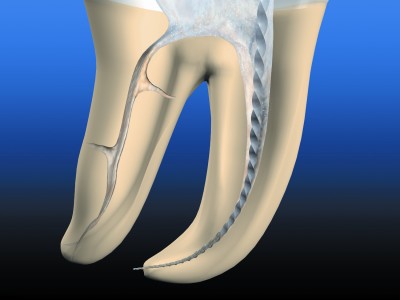

Пульпит- в процессе глубокого кариеса, продукты жизнедеятельности бактерий и распада проникают в пульпу (нерв), вызывая восспаление нерва. При пульпити необходимо эндодонтическое лечение и пломбирование корневых каналов зуба.

Материал для пломбирование каналов зуба индивидуален. Зависит от анатомии зуба, количество корней зубов, кривизны каналов зуба.